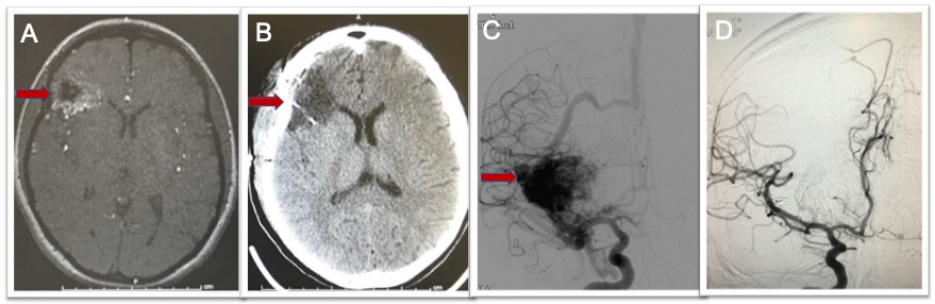

Figure 4. Brain AVM imaging techniques. A) MRI scan showing right frontal AVM (arrow). B) CT scan after surgery showing no remaining AVM. C) Brain angiogram before surgery showing the brain blood vessels and large AVM (arrow). D) Brain angiogram after surgery showing no remaining AVM and normal vessels filling.